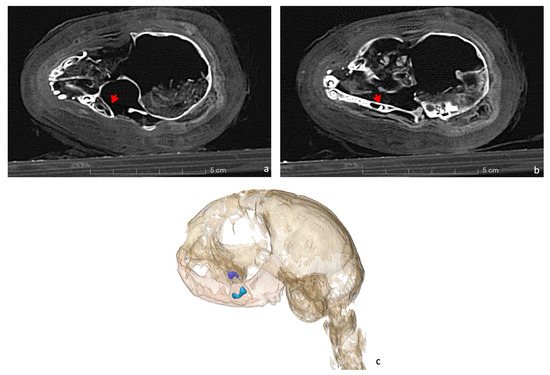

Moreover, the CT scans indicated the presence of materials within the cranium, resembling small bone fragments and the remnants of brain tissue (Figure 8).

Figure 8.

Axial CT scan reveals the evidence of possible brain tissue and tiny bone fragments inside the skull, which are lying on the left side of the mummy (red arrow).

An intriguing observation in the skull is the presence of various materials within the cranial cavity. There are tiny bone fragments, probably originating from the cribriform plate and the medial wall of the right orbit, which could be a consequence of the desiccation process, which could have compromised their structural integrity and made them highly fragile, causing them to break with minimal handling. Additionally, the possible remnants of brain tissue are observed, located on the left side of the temporal and occipital bone regions (refer to Figure 8). Several studies have reported the appearance of brain residues inside animal skulls due to the dehydration caused by the mummification process [36,52]. Although this could be a possible explanation for the presence of this material, further analysis is needed to clarify the issue.